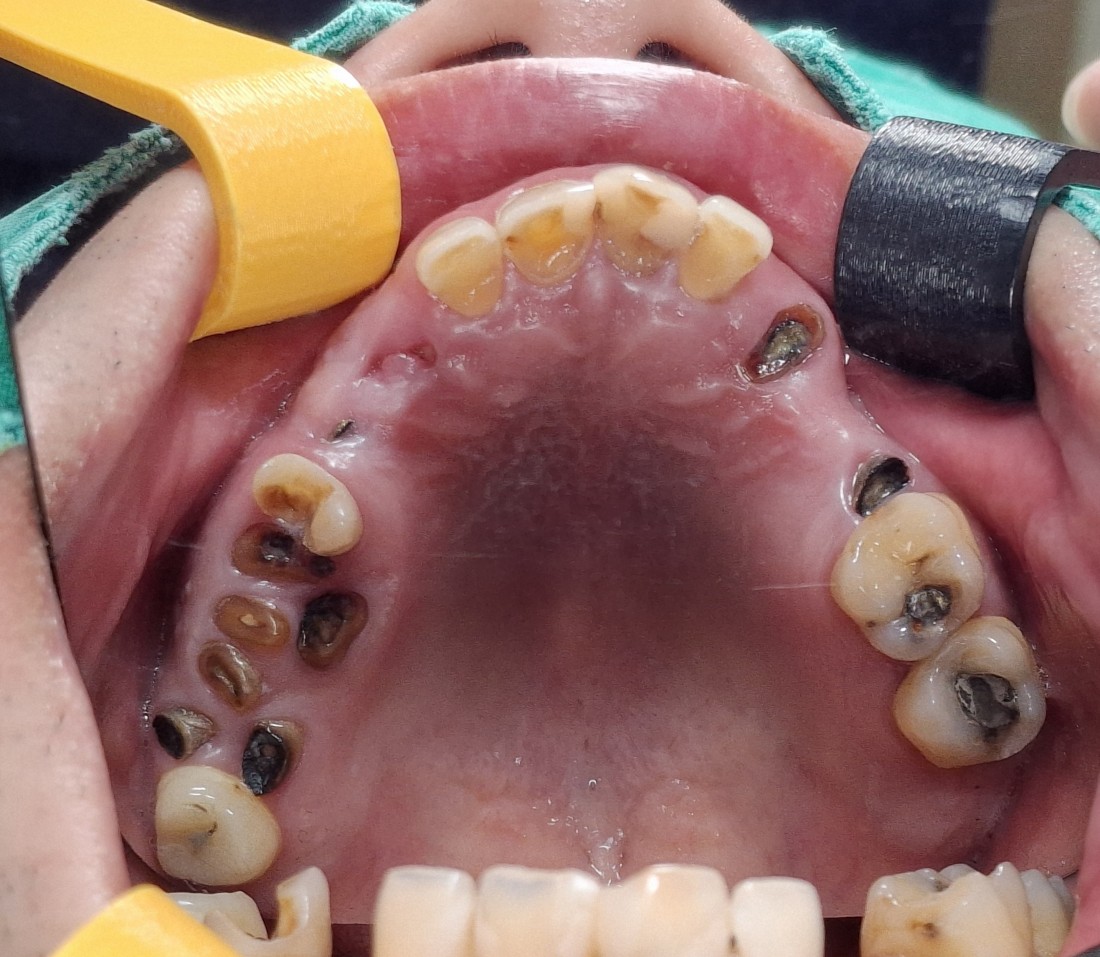

수완동 임플란트 치과에서는

임플란트 수술을 하기 전에

자연치아를 최대한 살려서

오래 사용하실 수 있도록

여러 진료를 추천해드리는데요.

그 중 하나인 잇몸치료는

보험이 적용되어

한 회당 2만원 대의 금액으로

2회 정도 수완동 치과에 내원하시면

잇몸염증을 해결하고

자연치아를 오래 사용할 수 있는

지름길이 되는 진료입니다.

수완동 임플란트 치과는

자연치아를 살릴 수 있는

최첨단 신경치료 기기를 도입하여

최소 통증의 치주치료가 가능합니다.

분과별 전문의 5인 대표원장의

협진 시스템으로

단 한 개의 치아라도 더 살리기 위해

최선을 다하고 있으며,

임플란트 수술이 필요한 경우에도

최소한의 개수만 식립하여

최대 효율을 얻을 수 있도록

진료시스템을 갖추고 있습니다.